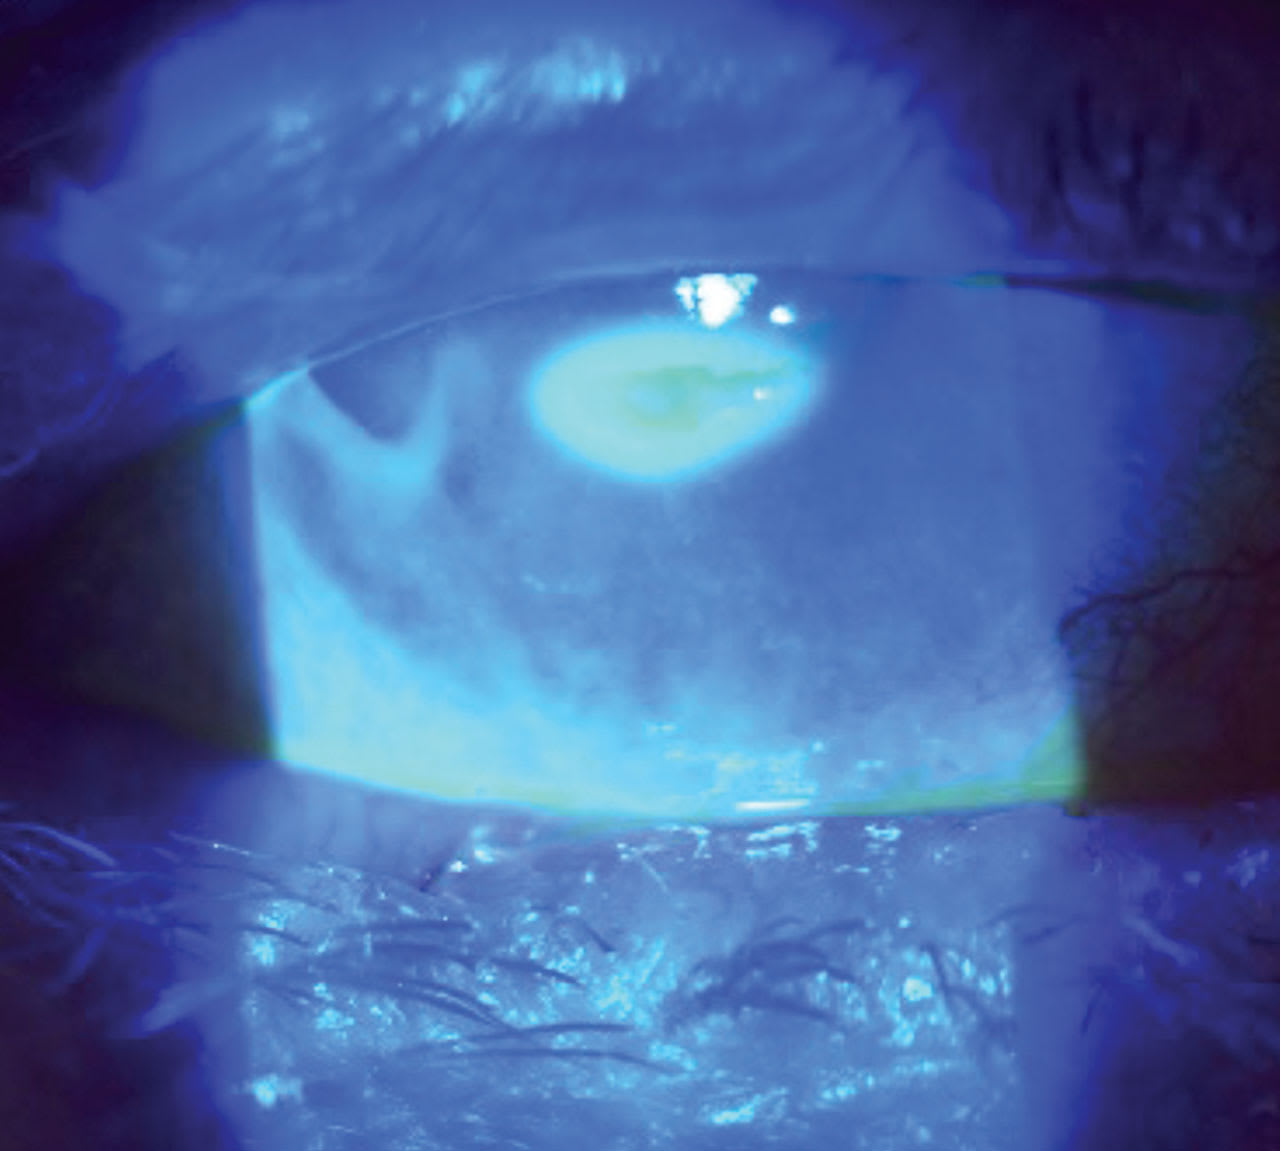

A 43-year-old female presented with pain, photophobia, and discharge for the past few months.

• Patient ocular history: dry eyes for the past 10 years, managed with over-the-counter artificial tears.

• Diagnosis: superficial punctate keratitis with epithelial defect (Figure 1).

• Treatment: dehydrated amniotic membrane contact lens (AMCL) 12mm biostability amnio graft was inserted in the bowl of soft contact lens, 8.4mm base curve radius (BCR); 14.0mm overall diameter (OAD); –0.50D.

• Follow-up at 48 hours demonstrated a clear cornea (Figure 2).